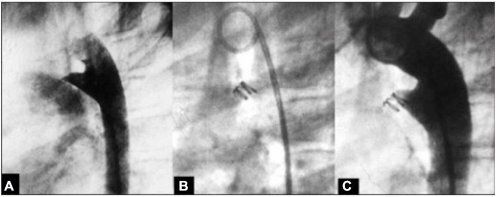

Na figura abaixo, observa-se uma oclusão de ducto arterioso. A: Canal arterial tipo A de 2 mm (milímetros) de diâmetro; B: Configuração helicoidal do dispositivo com uma alça na artéria pulmonar e duas alças na ampola aórtica; C: A ortografia de controle, evidenciando oclusão total.